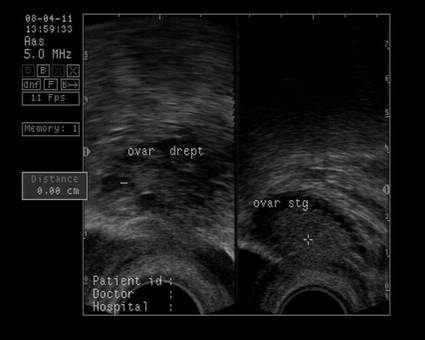

Ovarele. Sectiunea longitudinala directa, spre peretele lateral pelvin, la ecografia transvaginala, pune in evidenta ovarele cu forma elipsoidala. Acestea au structura ecografica relativ slab ecogena, in apropierea si sub vasele iliace.[5]

La pacientele care nu consuma contraceptive hormonale orale se pot identifica usor foliculii selectati preovulator sau corpul galben.

In postmenopauza, disparitia ecostructurii specifice cu foliculi anecogeni si atrofia ovarelor duce la identificarea ovarelor in proportie mult mai mica (de la 96% in premenopauza , scade identificarea ovarelor la 64%, prin ecografie transvaginala [6]).

Marimea ovarelor: inainte de menopauza aproximativ 3,5 x 2,5 x 1,5 cm si aproximativ 2,0 x 1,5 x 1 cm dupa menopauza. Nu se poate aprecia volumul ovarian decat masurand cele trei diametre in planuri sagitale, oblice si coronale ale pelvisului.[1,2,9]